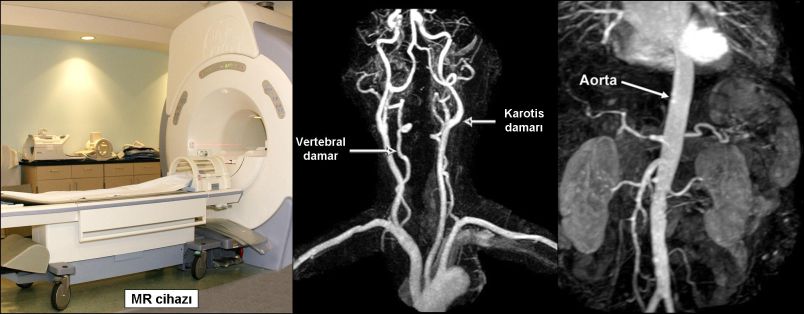

MR (Emar) anjiografi: MR anjiografide, hasta tüp şeklinde büyük bir mıknatısın içine yatırılarak manyetik alan ve radyo dalgalarından yararlanılarak damarlar görüntülenir. Hastaya hiç ilaç vermeden bile damarlar görüntülenebilir, ancak son yıllarda kol toplardamarından ilaç verilmesi tercih edilmektedir. MR ile vücuttaki tüm damarlar görüntülenebilir. Özellikle ultrasonografinin iyi gösteremediği beyin, göğüs ve karın bölgesindeki damarlar da çok iyi incelenebilir. Ayrıca tüm damarlar üç boyutlu olarak istenilen açıdan değerlendirilebilir.

MR anjiografinin en önemli üstünlükleri vücuttaki tüm damarları hastaya radyasyon vermeksizin gösterebilmesidir. Günümüzde en çok beyin, boyun, bacak ve karın damarlarında kullanılır. En önemli dezavantajı vücudumuzdaki kalp, damar ve barsak gibi organların hareketleri nedeniyle “artefakt” adı verilen bazı yanıltıcı görüntülerin oluşmasıdır. Bu nedenle normal olan bazı damarları daralmış, daralmış bazı damarları da tam tıkalı gibi gösterebilir. Ayrıca damar duvarında kireçlenme ve vücutta bulunan metal parçaları görüntüyü bozabilir. Bazı durumlarda da atardamar ve toplardamarlar birbirlerinden ayrılamayabilirler. Bu yüzden MR anjiografi tıpkı renkli Doppler ultrasonografi gibi damar hastalıklarının görüntülenmesinde bir “ön test” olarak kullanılır. Bu ön testlerde bir anormallik saptanırsa genellikle BT anjiografi ve klasik anjiografi gibi yöntemlerle ileri inceleme yapılır.